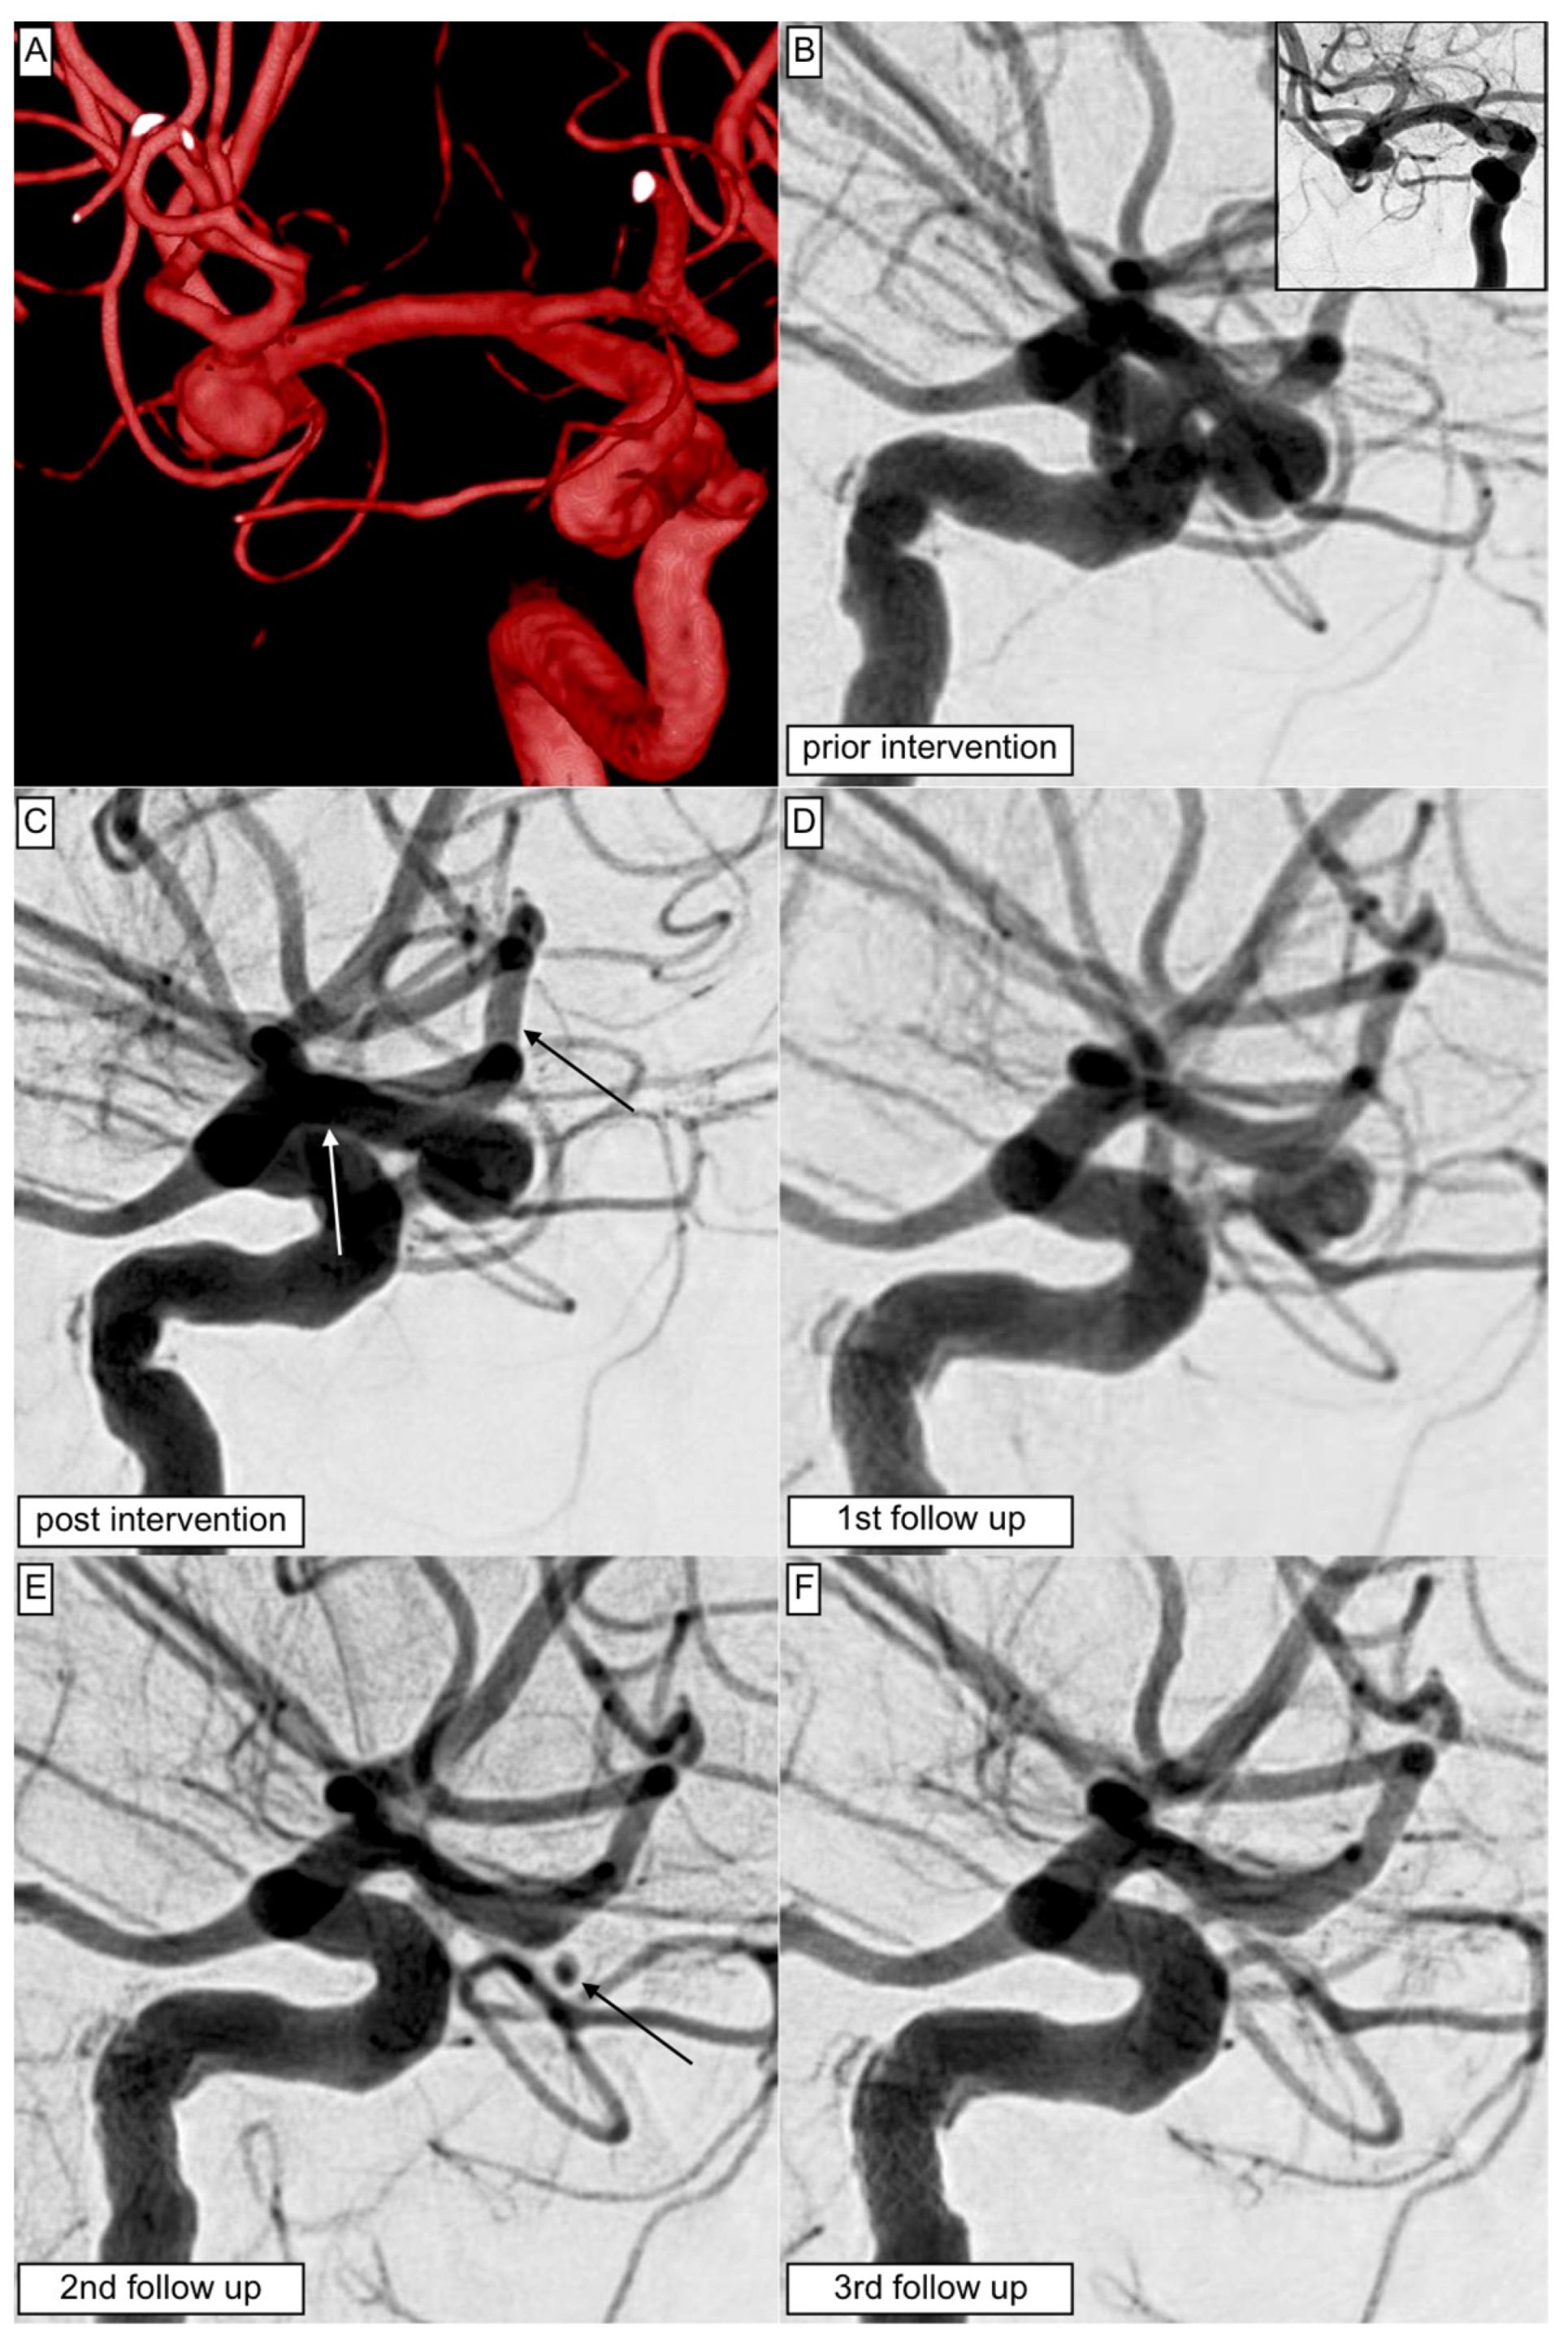

- Schüngel, M.-S.; Quäschling, U.; Weber, E.; Struck, M.F.; Maybaum, J.; Bailis, N.; Arlt, F.; Richter, C.; Hoffmann, K.-T.; Scherlach, C.; et al. Endovascular Treatment of Intracranial Aneurysms in Small Peripheral Vessel Segments-Efficacy and Intermediate Follow-Up Results of Flow Diversion With the Silk Vista Baby Low-Profile Flow Diverter. Front. Neurol. 2021, 12, 671915. [Google Scholar] [CrossRef]